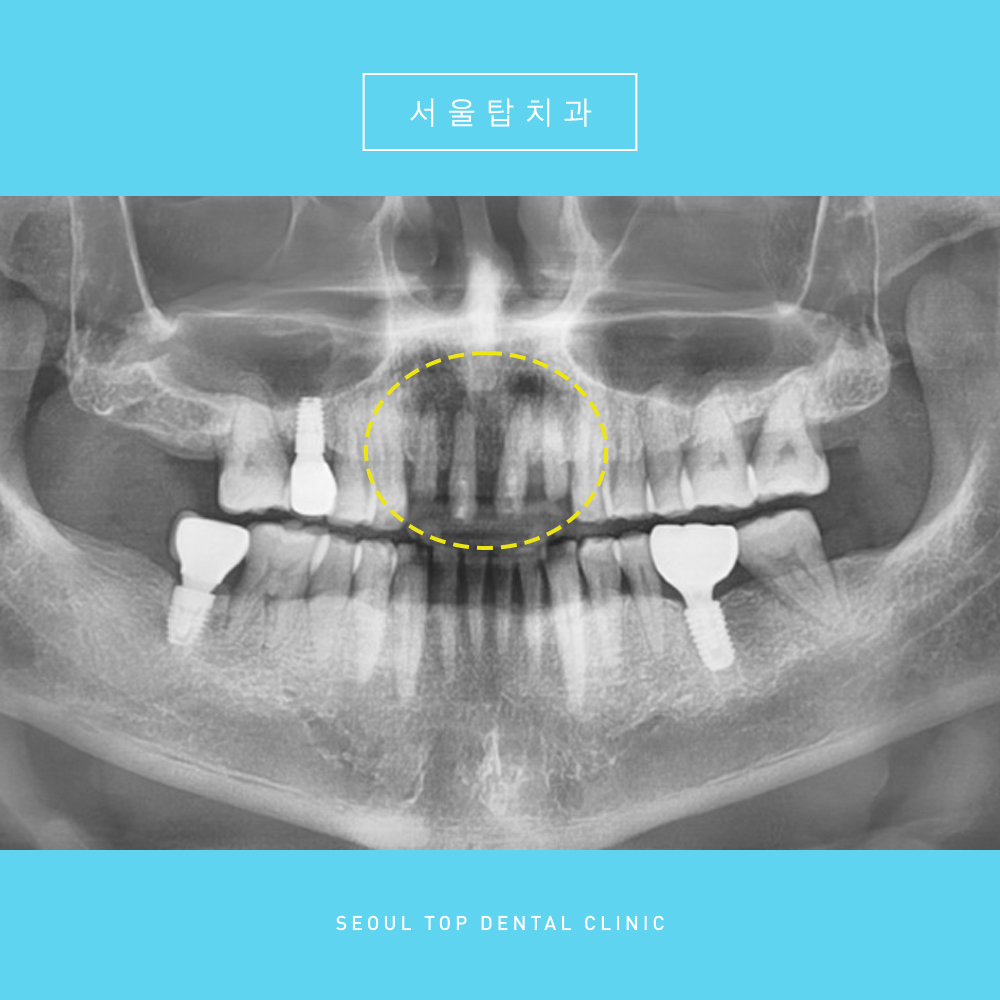

위 환자분은 과거 앞니에

크라운(보철물)을 씌우는 치료를 받으신 상황이었는데요.

환자분께서 불편감을 가지셔

보철물을 제거해보니

치아 뿌리 끝 주변으로 염증소견이 있었으며

치아 예후가 불량한 상태였습니다. 😭

환자분과 상담을 진행한 후,

앞니 4개를 발치하고 임플란트를 진행하기로 하였습니다.

총 4개를 발치하였는데,

임플란트는 2개를 식립하고 중간에 인공치를 달아

브릿지의 형태로 임플란트 치료를 도와드렸습니다.